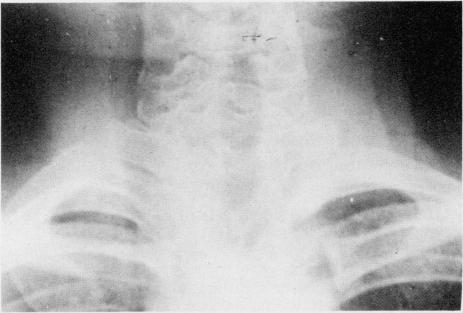

A Nigerian school boy with the syndrome of multiple jaw cysts, skeletal anomalies, and basal cell nevi is described and discussed. To the authors' knowledge, this is the first report of this syndrome in a black African.

本文描述并讨论了一名患有多颌囊肿、骨骼异常和基底细胞痣综合征的尼日利亚男学生。据作者所知,这是该综合征在非洲黑人中的首例报告。